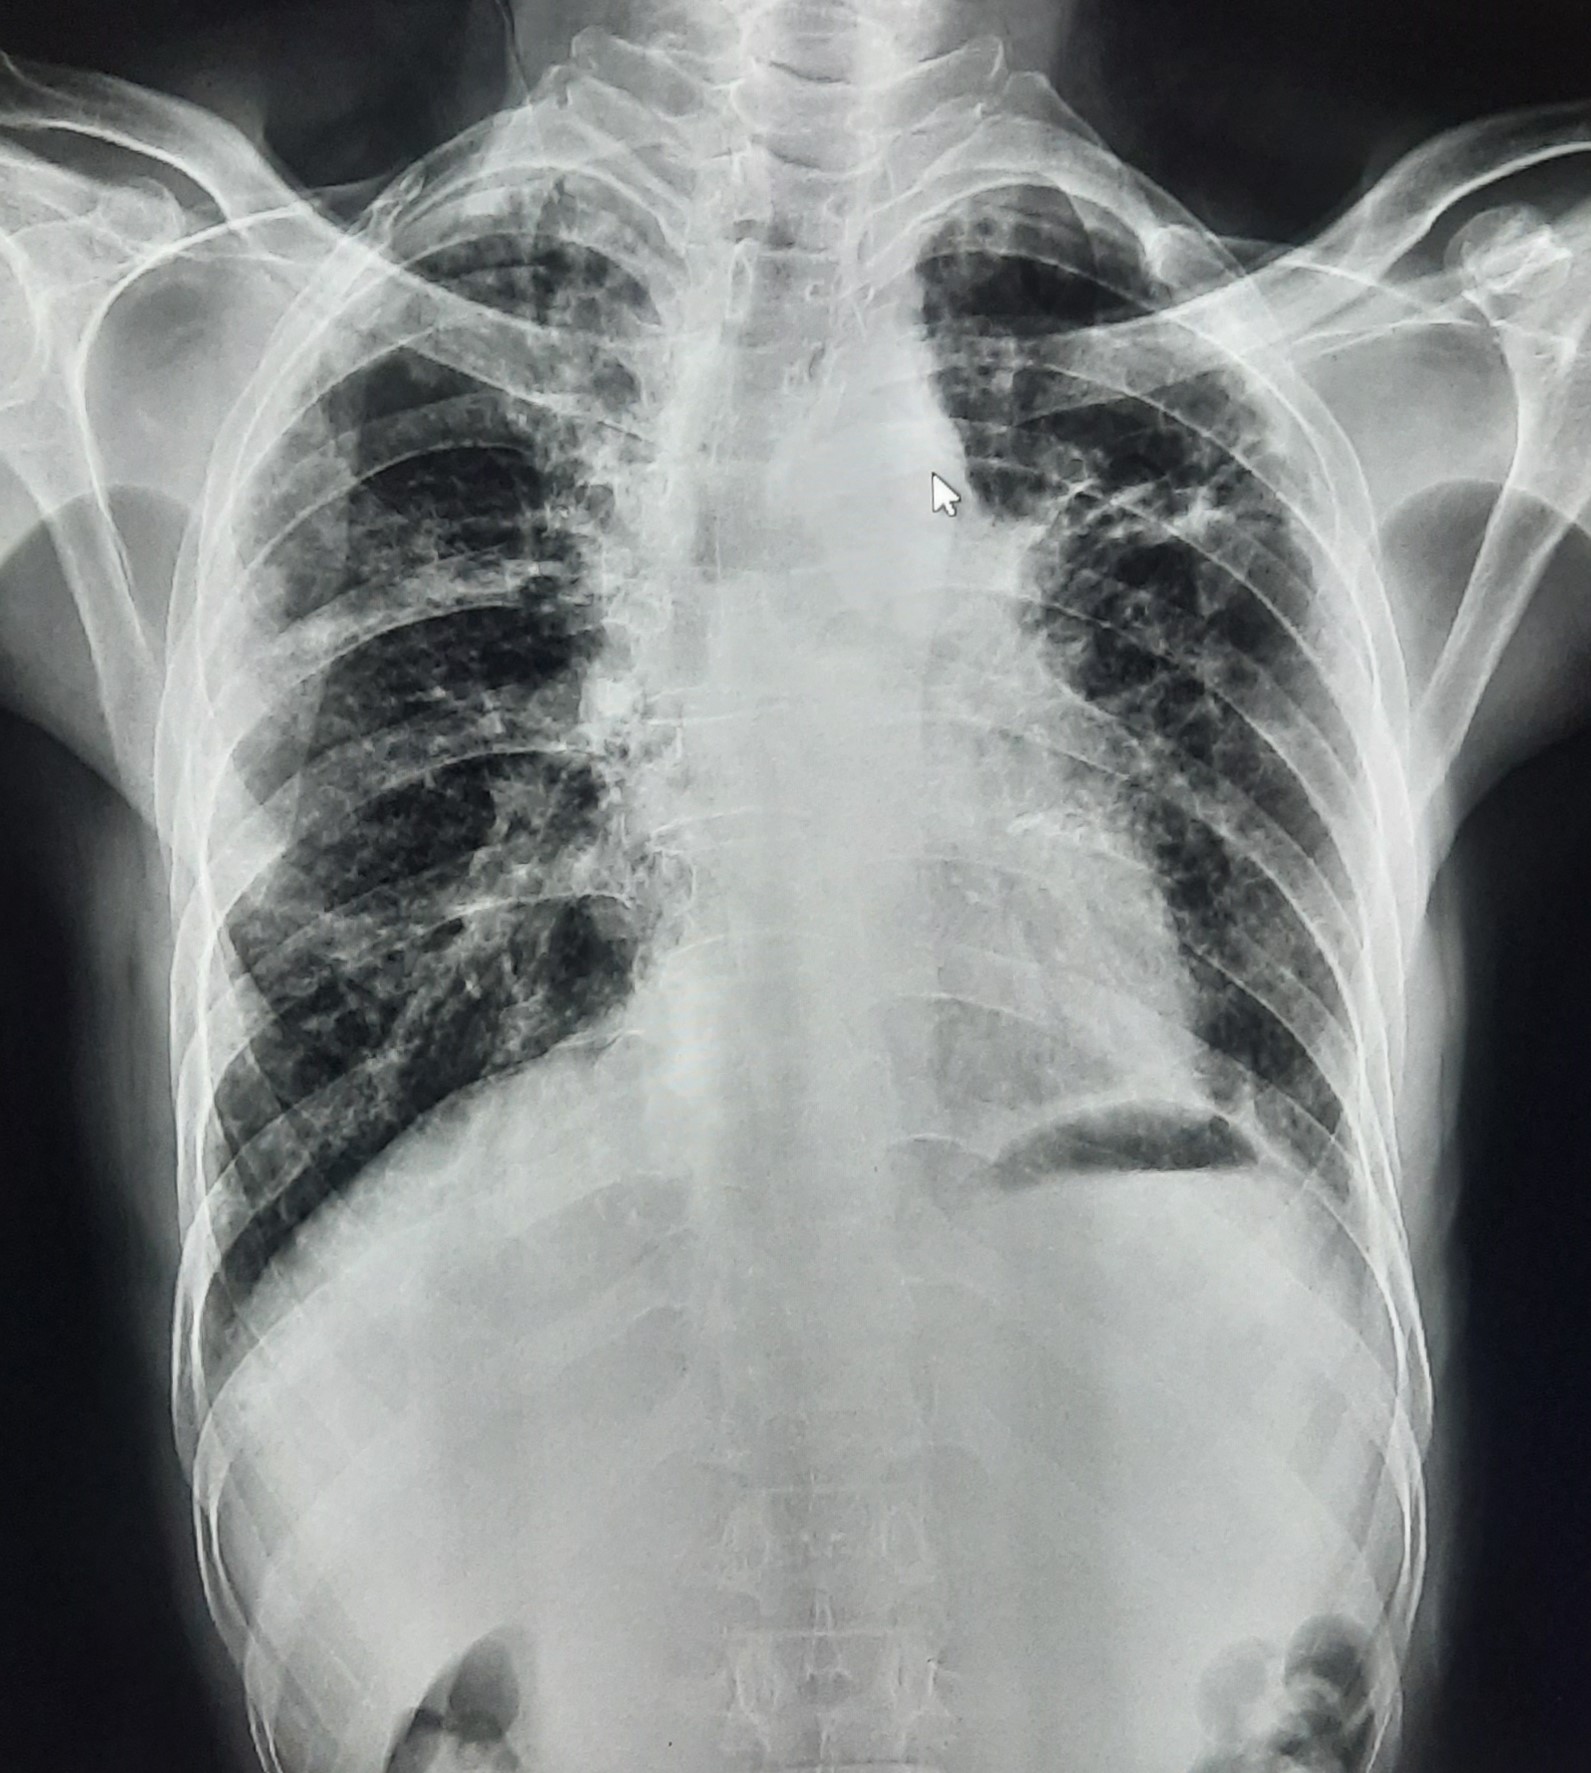

| 51 | IGGMC, Nagpur, Nagpur | P2 | 29-4421 | Santosh Neware | Consent taken on Paper | 40 Yrs. |

Provisional Diag : Pulmonary Tuberculosis

Final Diag : Pulmonary tuberculosis (Microbiologically Confirmed PTB) |

TB Case (Confirmed) | Right Upper & mid zone fibro cavitary lesion present, upward pull of right hemidiaphragm, tracheal pull right sided | Abnormality visible on x-ray |